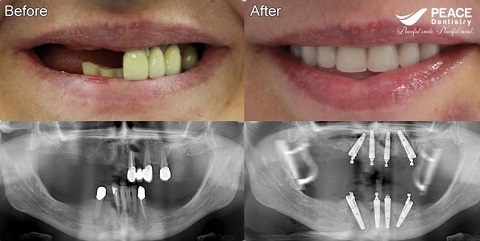

All on 6 dental implant for upper and lower jaw

All on 6 for upper jaw

All on 4 for lower jaw after 3 years of missing teeth